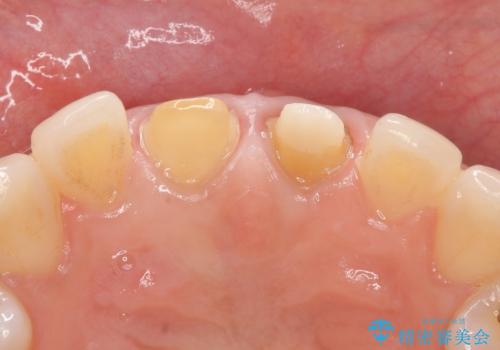

オールセラミッククラウン 変色が気になる前歯の治療

- 前歯の変色が気になるのでセラミックによる治療を行いたいといらっしゃった方の症例です。

左上1番目の歯の再根管治療終了後、左右1番目の2歯をオールセラミッククラウンで補綴しました。

- オールセラミッククラウン…¥100,000×2、仮歯…¥10,000×2、ファイバーコア…¥20,000費用は治療当時の料金となります